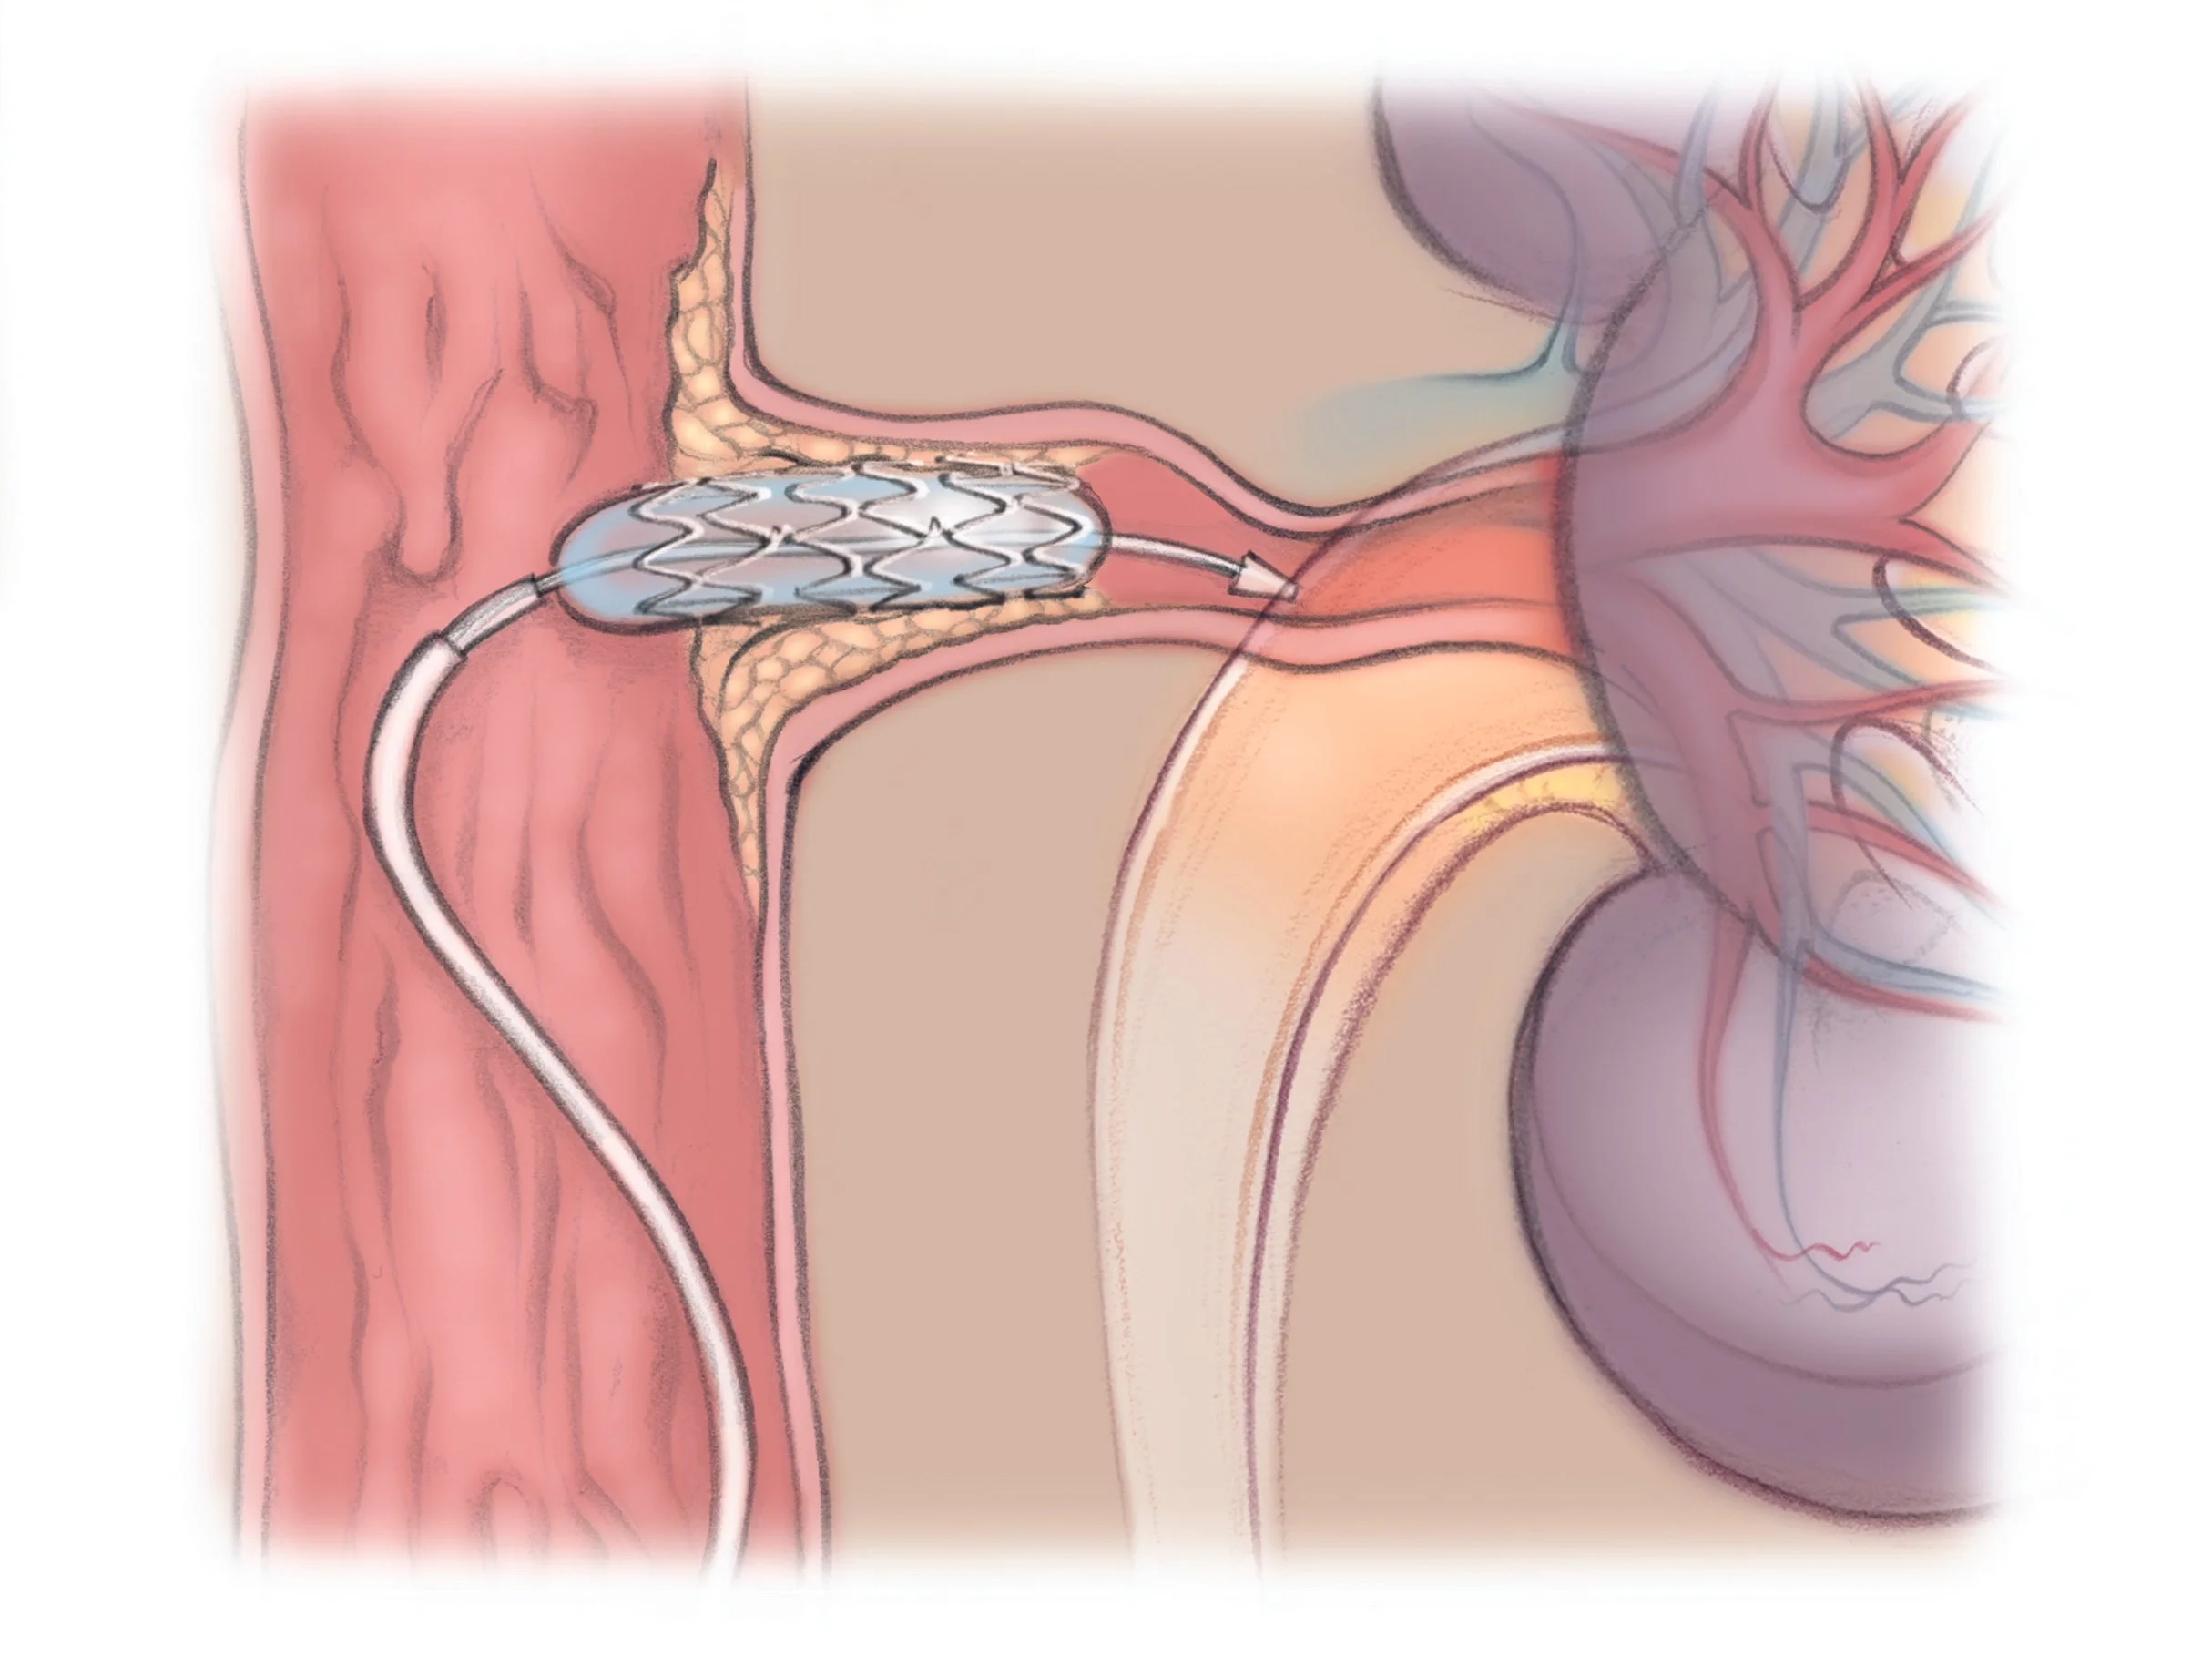

Renal artery stenting involves the placement of a small, metal mesh tube called a stent inside the narrowed renal artery. The stent acts as a scaffold to hold the artery open, preventing it from collapsing or becoming blocked again. This procedure is typically performed using a catheter-based technique known as percutaneous transluminal renal angioplasty (PTRA). During the procedure, a balloon catheter is threaded through the blood vessels to the site of the narrowing. The balloon is inflated to widen the artery, and then the stent is deployed to keep the artery open.

Renal artery stenting is performed in a catheterization laboratory under local anesthesia, often with mild sedation. The interventional radiologist or vascular specialist inserts a catheter, usually through the femoral artery in the groin, and guides it to the renal artery using real-time X-ray imaging (fluoroscopy). Once the catheter reaches the narrowed segment, a balloon is inflated to dilate the artery, and the stent is placed to maintain vessel patency.

To minimize embolic complications, embolic protection devices such as the GuardWire may be used during the procedure. These devices capture debris that might otherwise travel downstream and cause blockages.